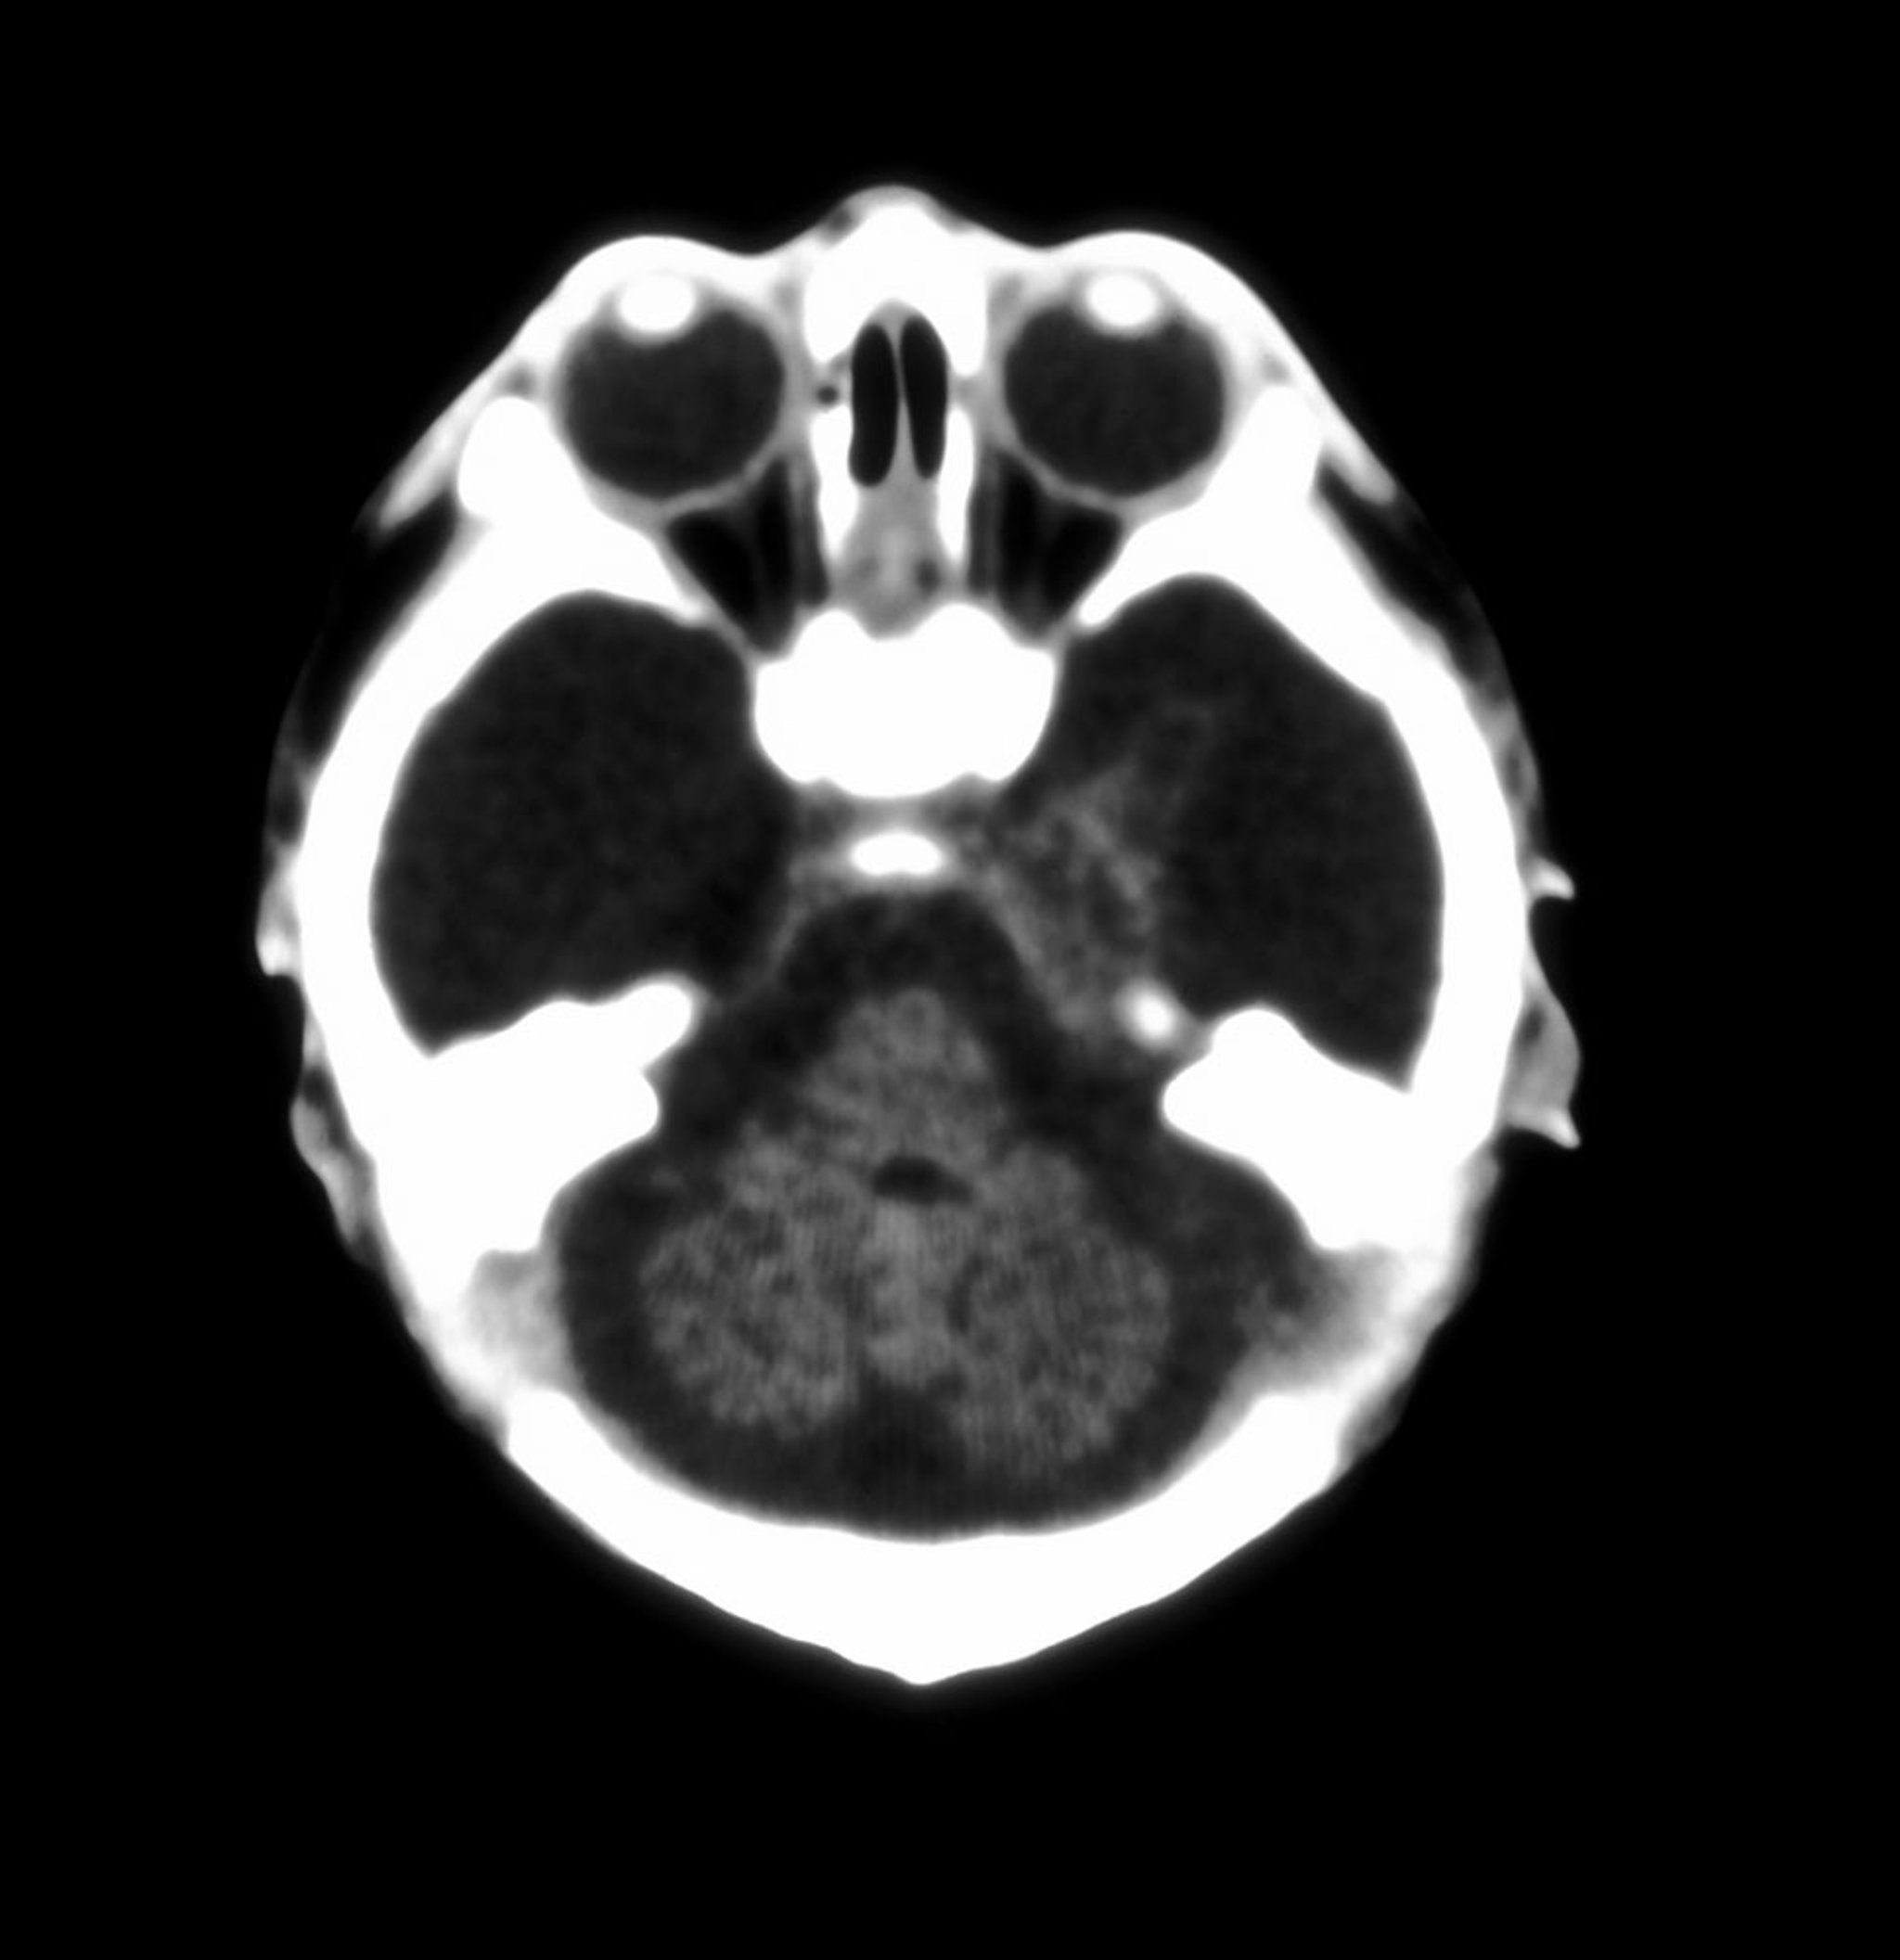

This axial CT image of the brain in a neonate shows almost total absence of the cerebral hemispheres.

Hydranencephaly is an extreme form of porencephaly in which the cerebral hemispheres are almost totally absent. Usually, the cerebellum and brain stem are formed normally, and the basal ganglia are intact. The meninges, bones, and skin over the cranial vault are normal.

In hydranencephaly, cyst formation usually is caused by massive interruption of the blood supply to the developing hemispheres after the 12th week of pregnancy. The blood supply is interrupted by bilateral large-vessel strokes in utero. The skull of an affected infant does not have a defect in this case, and externally the infant may appear normal. The infant may be capable of normal infantile reflex movements, such as sucking and grasp, but does not progress further developmentally.